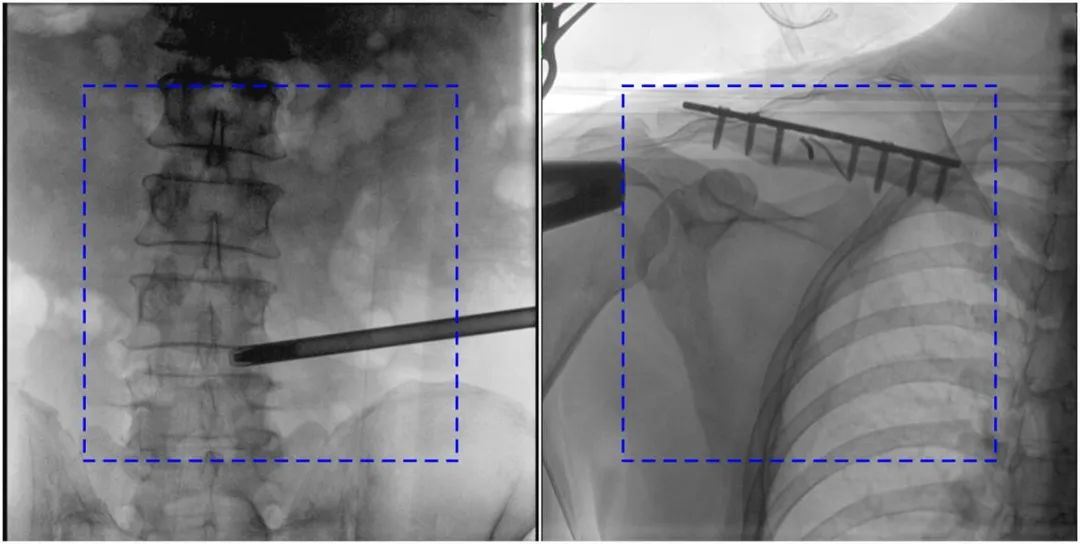

與傳統(tǒng)的21CM×21CM成像尺寸相比,普愛醫(yī)療大平板一體式C形臂具有30CM×30CM更大成像尺寸,能夠一次成像5.5節(jié)椎體,呈現(xiàn)更全面的影像信息,即便是手術(shù)經(jīng)驗(yàn)不豐富的年輕醫(yī)生也能通過(guò)圖像迅速判斷椎體節(jié)段、定位手術(shù)部位,避免因?yàn)橐曇安蛔愣斐傻亩啻味ㄎ?、反?fù)曝光,提高效率的同時(shí)避免過(guò)量攝入輻射。

普愛醫(yī)療大平板一體式C形臂圖像與傳統(tǒng)圖像對(duì)比(藍(lán)色虛線內(nèi)為傳統(tǒng)21CM×21CM平板的成像區(qū)域)